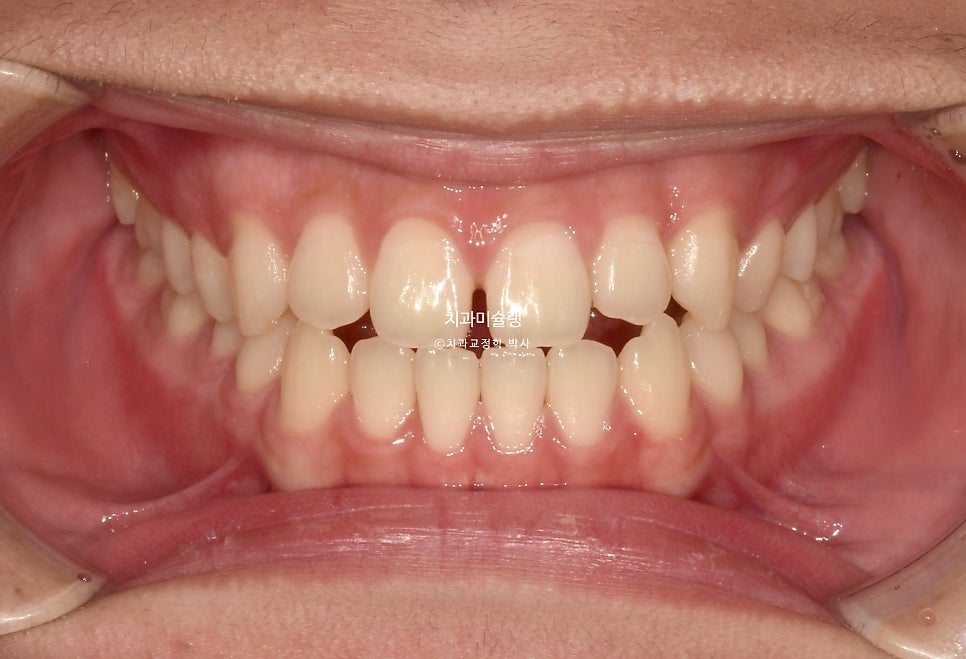

초진 시 구강 상태

제작년 유학중 여름방학을 맞이해 찾아온 만 15세 친구 입니다.

어릴때부터 소아치과에서 주기적으로 체크를 받아오며 교정이 필요없다는 이야기를 들었으나

최근 유학중 1-2년 사이 아래턱이 자란것같아 교정이 필요해보여 내원했습니다.

위 앞니가 벌어져있고 일부 개방교합이 보입니다.

어금니 교합관계는 3급이며 윗니가 아랫니를 덮지 못하는 절단교합 입니다.